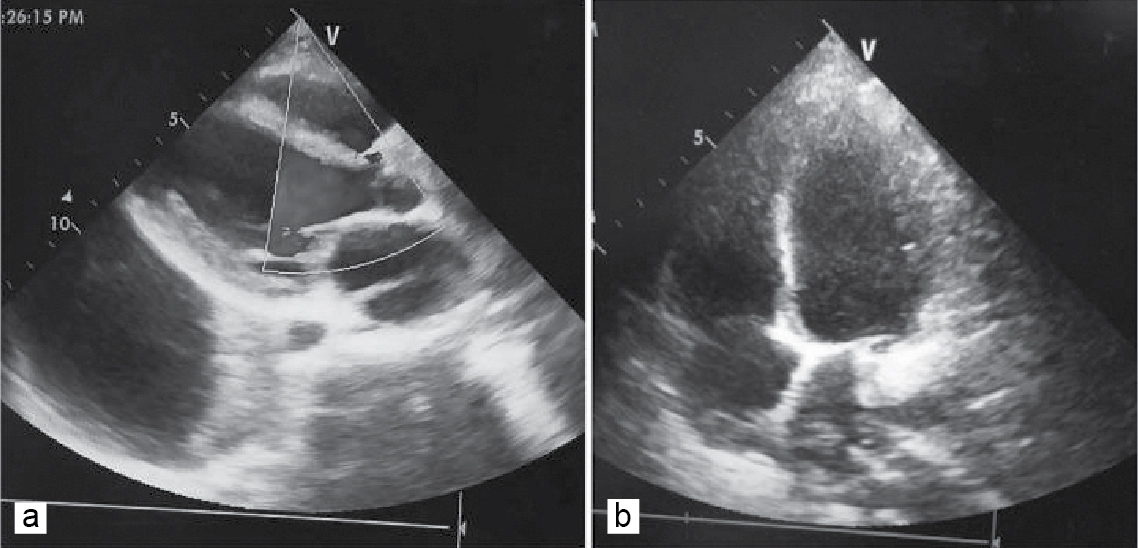

On examination, blood pressure was found to be 70/50 mmHg. ECG was suggestive of multiple ventricular premature complexes (Fig. 1). Myocarditis secondary to scrub typhus was suspected. Cardiac enzymes were elevated (Troponin T - 0.86 ng/mL, creatine phosphokinase-MB - 68 ng/mL). Patient was started on inotropes, injection magnesium sulfate and injection hydrocortisone. A two-dimensional echocardiography (2D-Echo) was done which revealed mild mitral and tricuspid regurgitation (Fig. 2 a and b) and global hypokinesia of left ventricle with an ejection fraction (EF) of 25%.

Figure 2 a and b. Echocardiographic still images showing mild mitral and tricuspid regurgitation with normal left atrial and ventricular size.